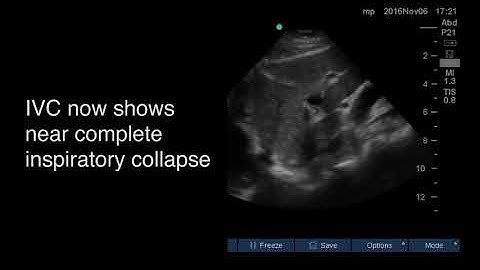

IVC Collapse Duration Classifications No, Brief, Intermediate and Extended by Zhou et al